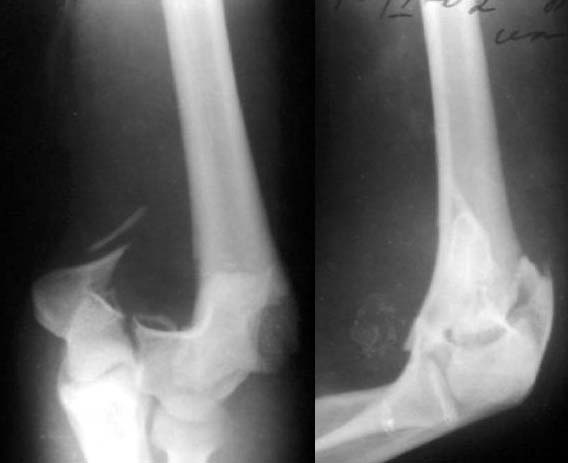

До лечения

Результат в 6 месяцев

Лечение тут, видимо, должно основываться в первую очередь на открытой репозиции, поскольку возможности закрытой при таких повреждениях далеко недостаточны. Если поверхность блока состоит не просто из двух крупных фрагментов, лучше идти с отсечением локтевого отростка. Вопрос о методе фиксации более второстепенный. Можно и аппаратом. В приложении - пример лечения такого повреждения с внутренней фиксацией.